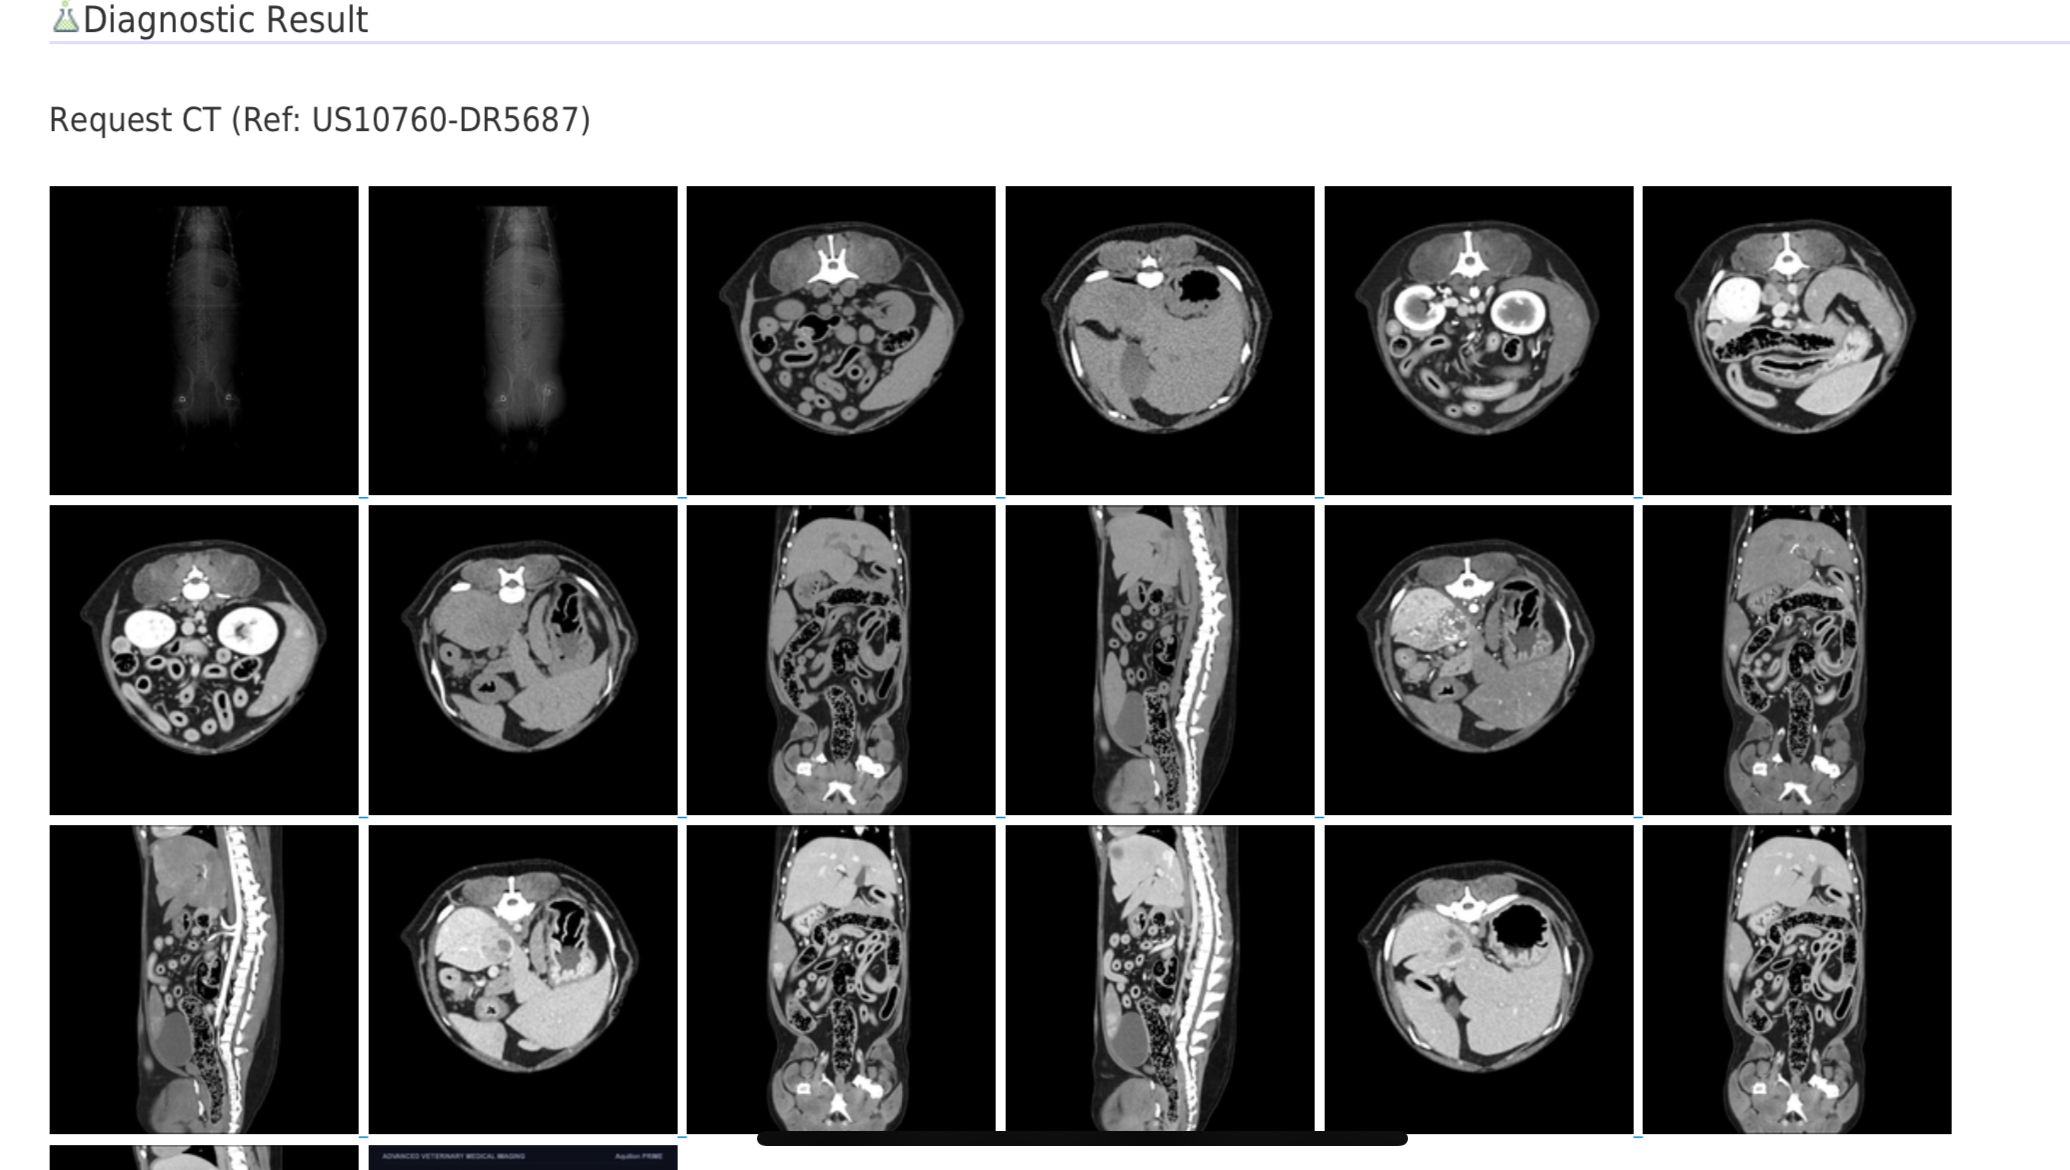

After seeking a second opinion it was suggested that Roscoe undergo x-rays and an ultrasound. The ultrasound revealed that Roscoe had developed a 1.6 cm tumor on his right adrenal gland with suspected invasion of his caudal vena cava. The CVC is a major vein in the body if not the largest. After referring to a surgical specialist who then referred us to an imaging center for a CT scan, we found out that the tumor had major invasion of the CVC. The tumor also has resulted to be a pheochromocytoma. It is one of the rarest tumors, only 1-2% of tumors are pheochromocytoma. At this time it does not appear to be cancerous as it has not metastasized.